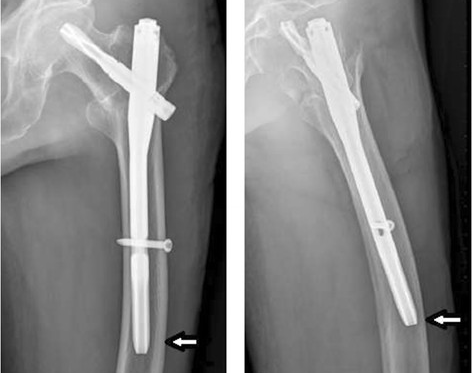

Le clou PFNA est un clou intramédullaire spécialement conçu utilisé en chirurgie orthopédique pour stabiliser les fractures du fémur proximal.Il se compose d'une longue tige métallique étroite qui est insérée dans le canal intramédullaire du fémur, s'étendant de la hanche au genou.La conception unique du clou PFNA permet une stabilité en rotation, des propriétés de répartition de la charge et une meilleure cicatrisation des fractures.

Le clou PFNA est principalement indiqué pour le traitement de diverses fractures de la hanche, y compris les fractures intertrochantériennes, les fractures sous-trochantériennes et certaines fractures du col du fémur.Il est particulièrement efficace dans les cas où une fixation stable est nécessaire pour favoriser une mise en charge et une mobilité précoces.

Insertion et fixation des clous: Le clou PFNA est soigneusement inséré sur la broche conductrice, assurant un alignement correct et évitant d'endommager les structures environnantes.Des vis sont utilisées pour fixer le clou en place.